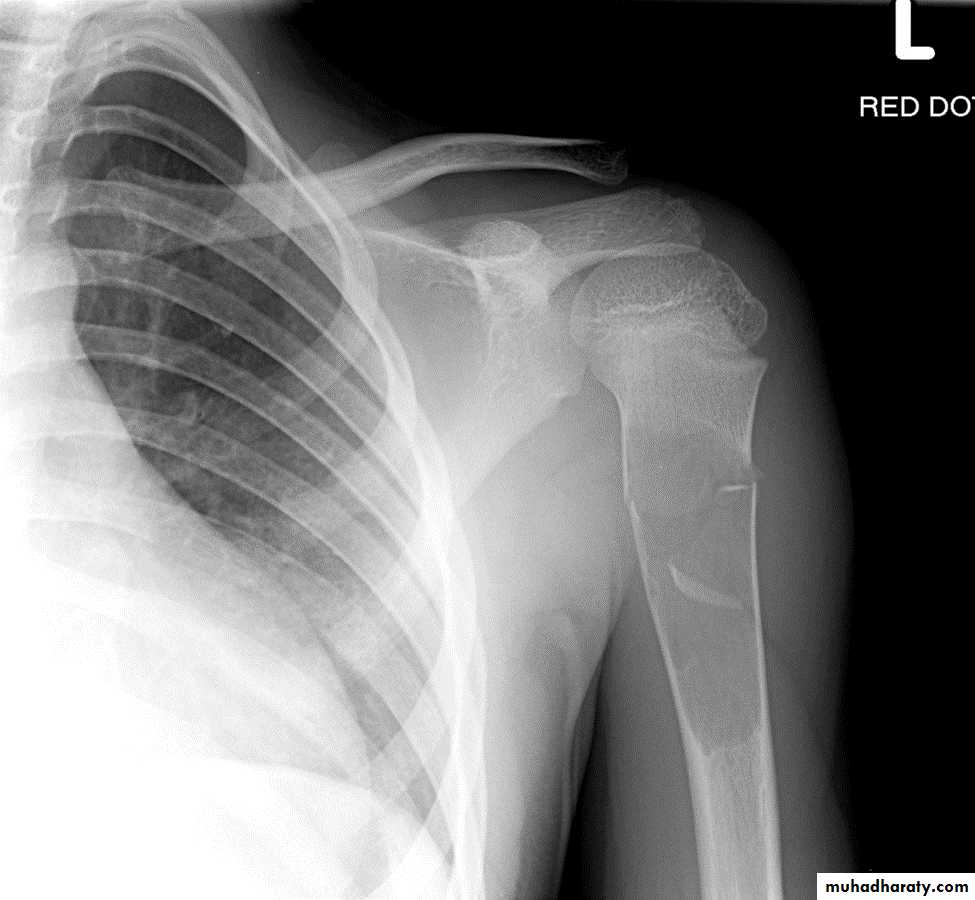

Giant cell tumor:Slowly growing , locally invasive, rarely metastasize.

Age: after closure of epiphysis (20-40 years).

Site: around knee & wrist joints.

Findings:

lytic, expansile lesion,

Sub articular in location,

Not clearly defined margin,

thinning of the cortex (sometimes with destruction of cortex)